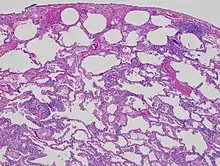

| High magnification photomicrograph of a lung biopsy taken showing chronic hypersensitivity pneumonitis (H&E), showing mild thickening of the walls of the small air sacs by invasion of white blood cells. A multinucleated giant cell, seen within the walls of the air sacs to the right of the picture halfway down, is an important clue to the correct diagnosis. | |

Lung biopsy

Lung biopsies can be diagnostic in cases of chronic hypersensitivity pneumonitis, or may help to suggest the diagnosis and trigger or intensify the search for an allergen. The main feature of chronic hypersensitivity pneumonitis on lung biopsies is expansion of the interstitium by lymphocytes accompanied by an occasional multinucleated giant cell or loose granuloma.[7][22]

When fibrosis develops in chronic hypersensitivity pneumonitis, the differential diagnosis in lung biopsies includes the idiopathic interstitial pneumonias.[23] This group of diseases includes usual interstitial pneumonia, non-specific interstitial pneumonia and cryptogenic organizing pneumonia, among others.[7][22]